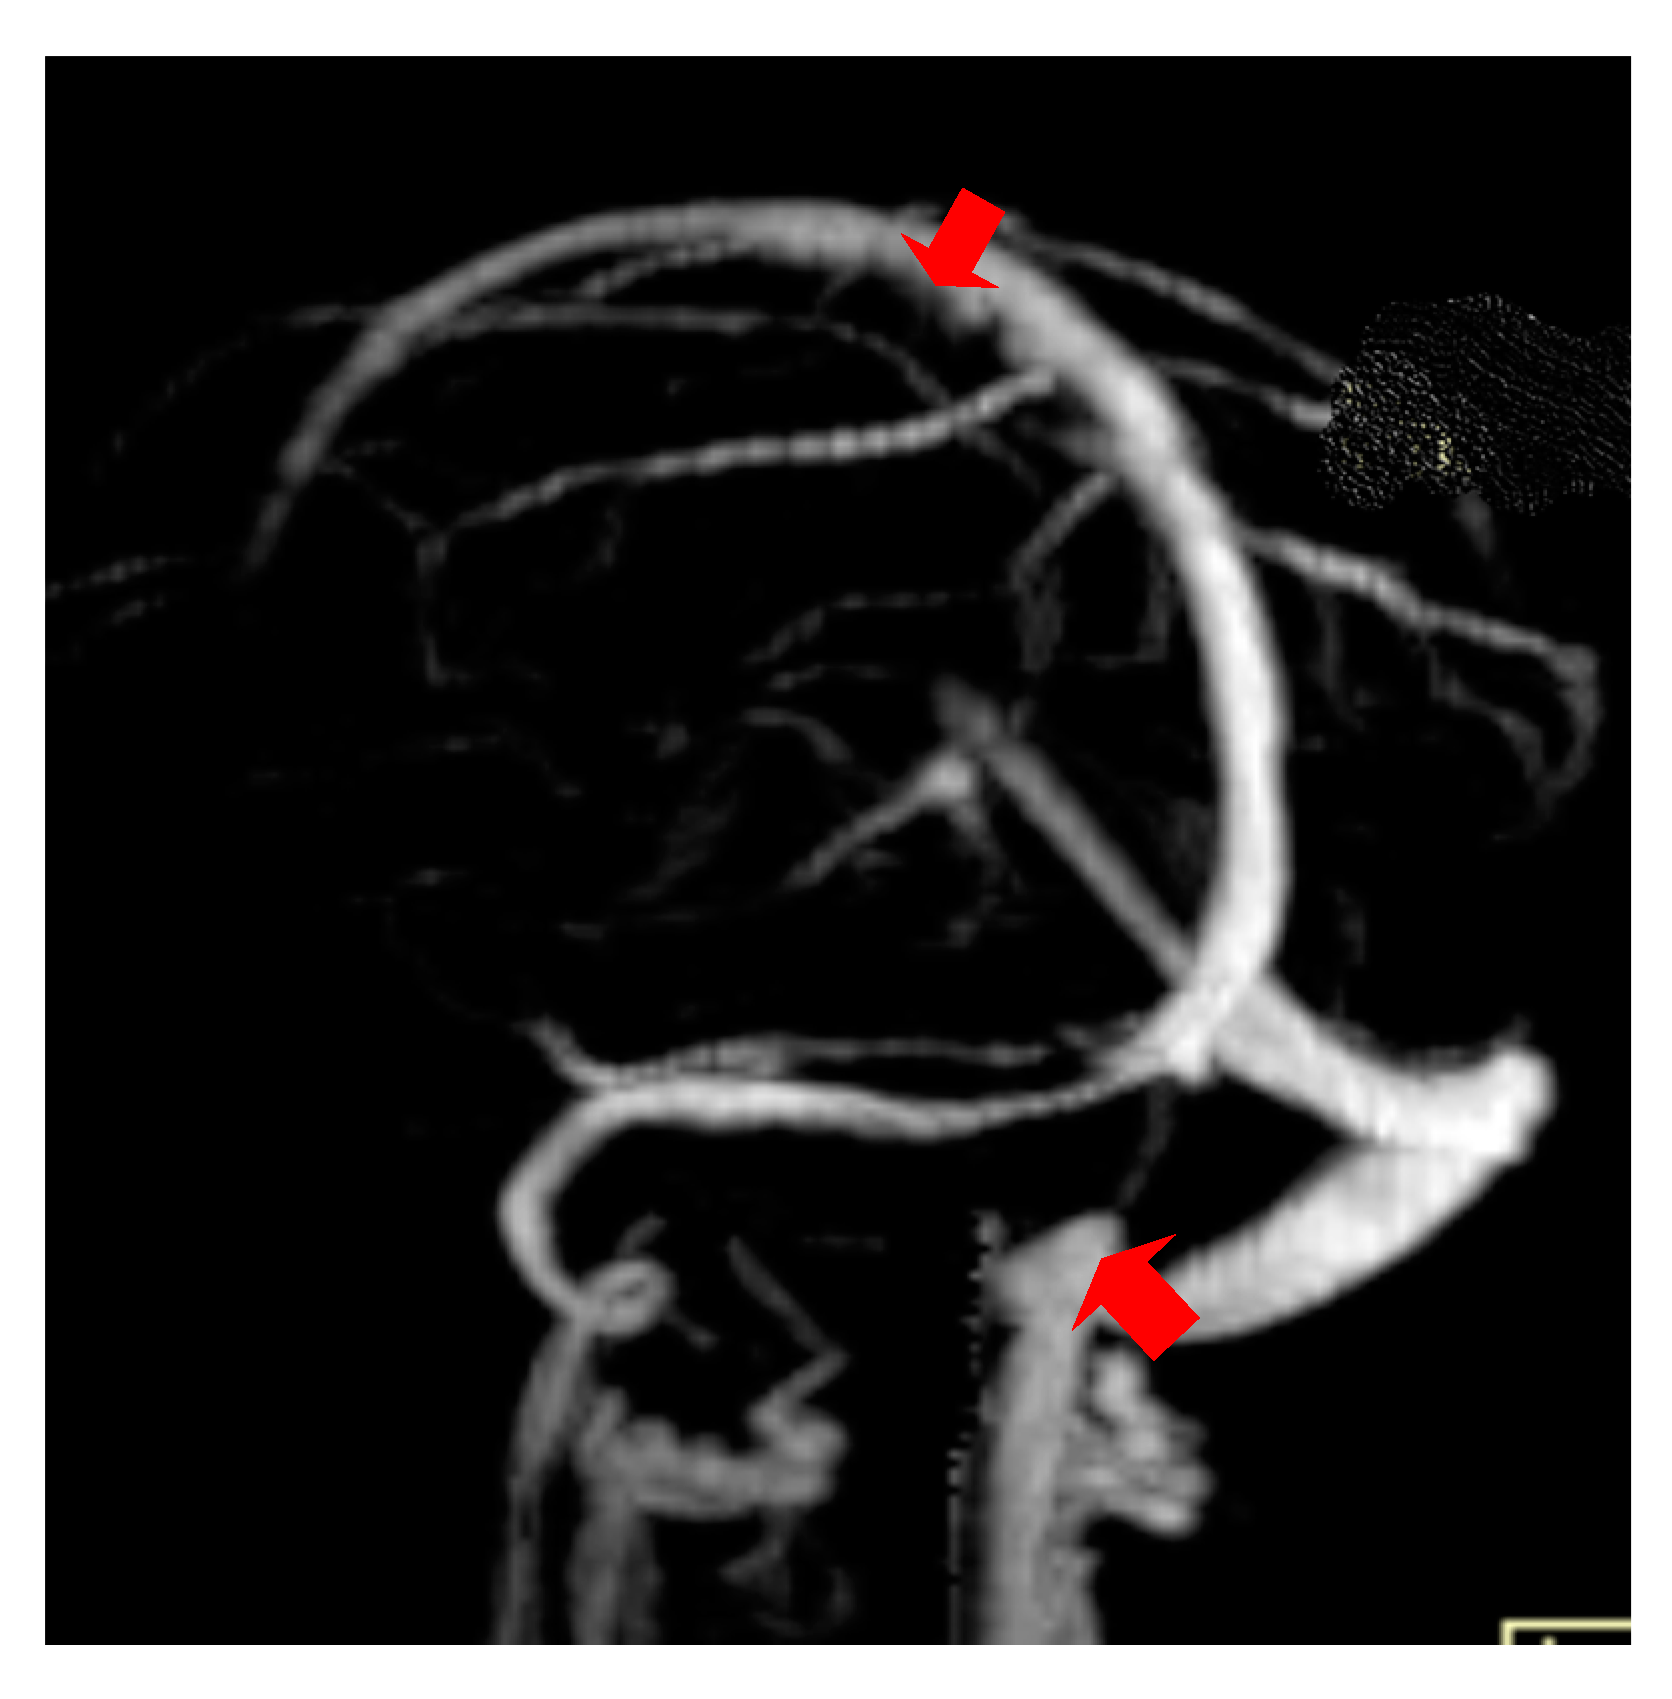

The second case was a female, 31 years old, with an etiology of thrombophlebitis accentuated by the presence of the MTHFR C677T gene polymorphism- homozygous phenotype. The patient was hospitalized with superficial coma, generalized seizures and left hemiparesis. In the course of evolution, subsequent to the cerebral post thrombotic syndrome and edematous encephalopathy, the patient presented symptomatology characterized by generalized seizures under anticonvulsivant treatment and also psychical disturbances (irritability, aggressiveness). The patient was clinically and neuroimagistic assessed after six month and six years from the onset of the disease. The image features can be seen in Figure 3, Figure 4 and Figure 5.

Figure 3. MR- venography Maximum Intensity Projection (MIP) range reveals thrombosis of the superior sagittal sinus and the right lateral sinus at the onset.